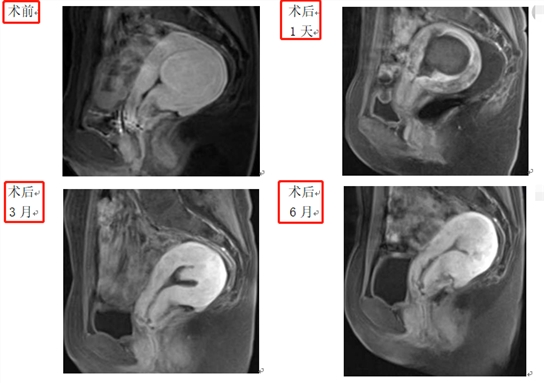

经过分析,沈女士被转诊到妇产科子宫肌瘤专科门诊,结合盆腔MRI增强诊断为II型粘膜下子宫肌瘤,肌瘤大小46x39mm。由于害怕手术及腹部出现瘢痕,科室经过沟通,为她制定了恢复快、损伤小、不开刀的治疗方案,即高强度聚焦超声消融术治疗子宫肌瘤。

完善术前准备后,妇产科立即安排了聚焦超声消融手术,全程2小时,术后即实现自行下床返回病房,术后第二天出院。术后1月,沈女士月经量及痛经较前变化不大,出血同时伴有少许组织物排出;术后2月后,月经量由较多变为正常月经量,痛经完全消失,贫血也在经量改善过程中纠正;术后6月,复查盆腔MRI增强子宫肌瘤大小由46x39mm缩小到18x11mm,遂行经阴道宫腔镜下子宫肌瘤切除术。最终,经术后1年复查,沈女士妇科彩超子宫上未见明显病灶,她对此种治疗方式感到非常满意。